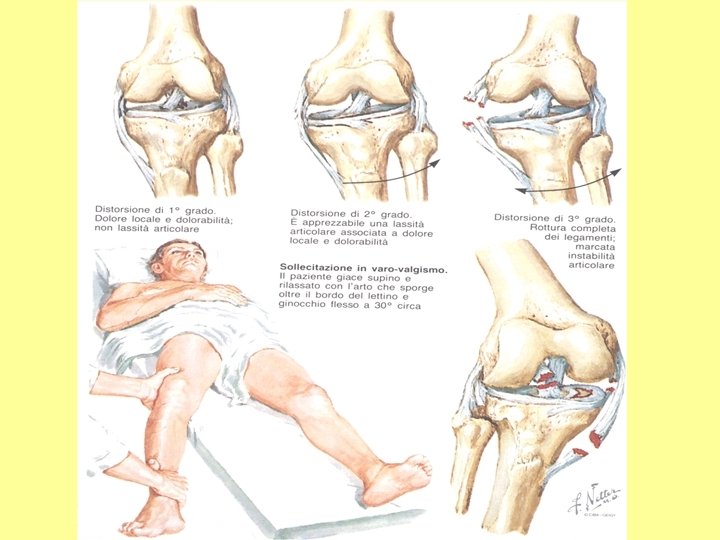

PATOLOGIE TRAUMATICHE A CARICO DELL’APPARATO LOCOMOTORE Frattura: rottura di una o più ossa (composta, scomposta, esposta, biossea, pluriframmentaria). Lussazione: fuoriuscita di una articolazione dal suo normale abitacolo (frattura – lussazione). Distorsione/distrazione: lesioni meniscali, capsulari e legamentose. Contusione: interessamento dei sottocute e della cute (ematoma). muscoli, Politrauma: interessa più organi e/o apparati. del